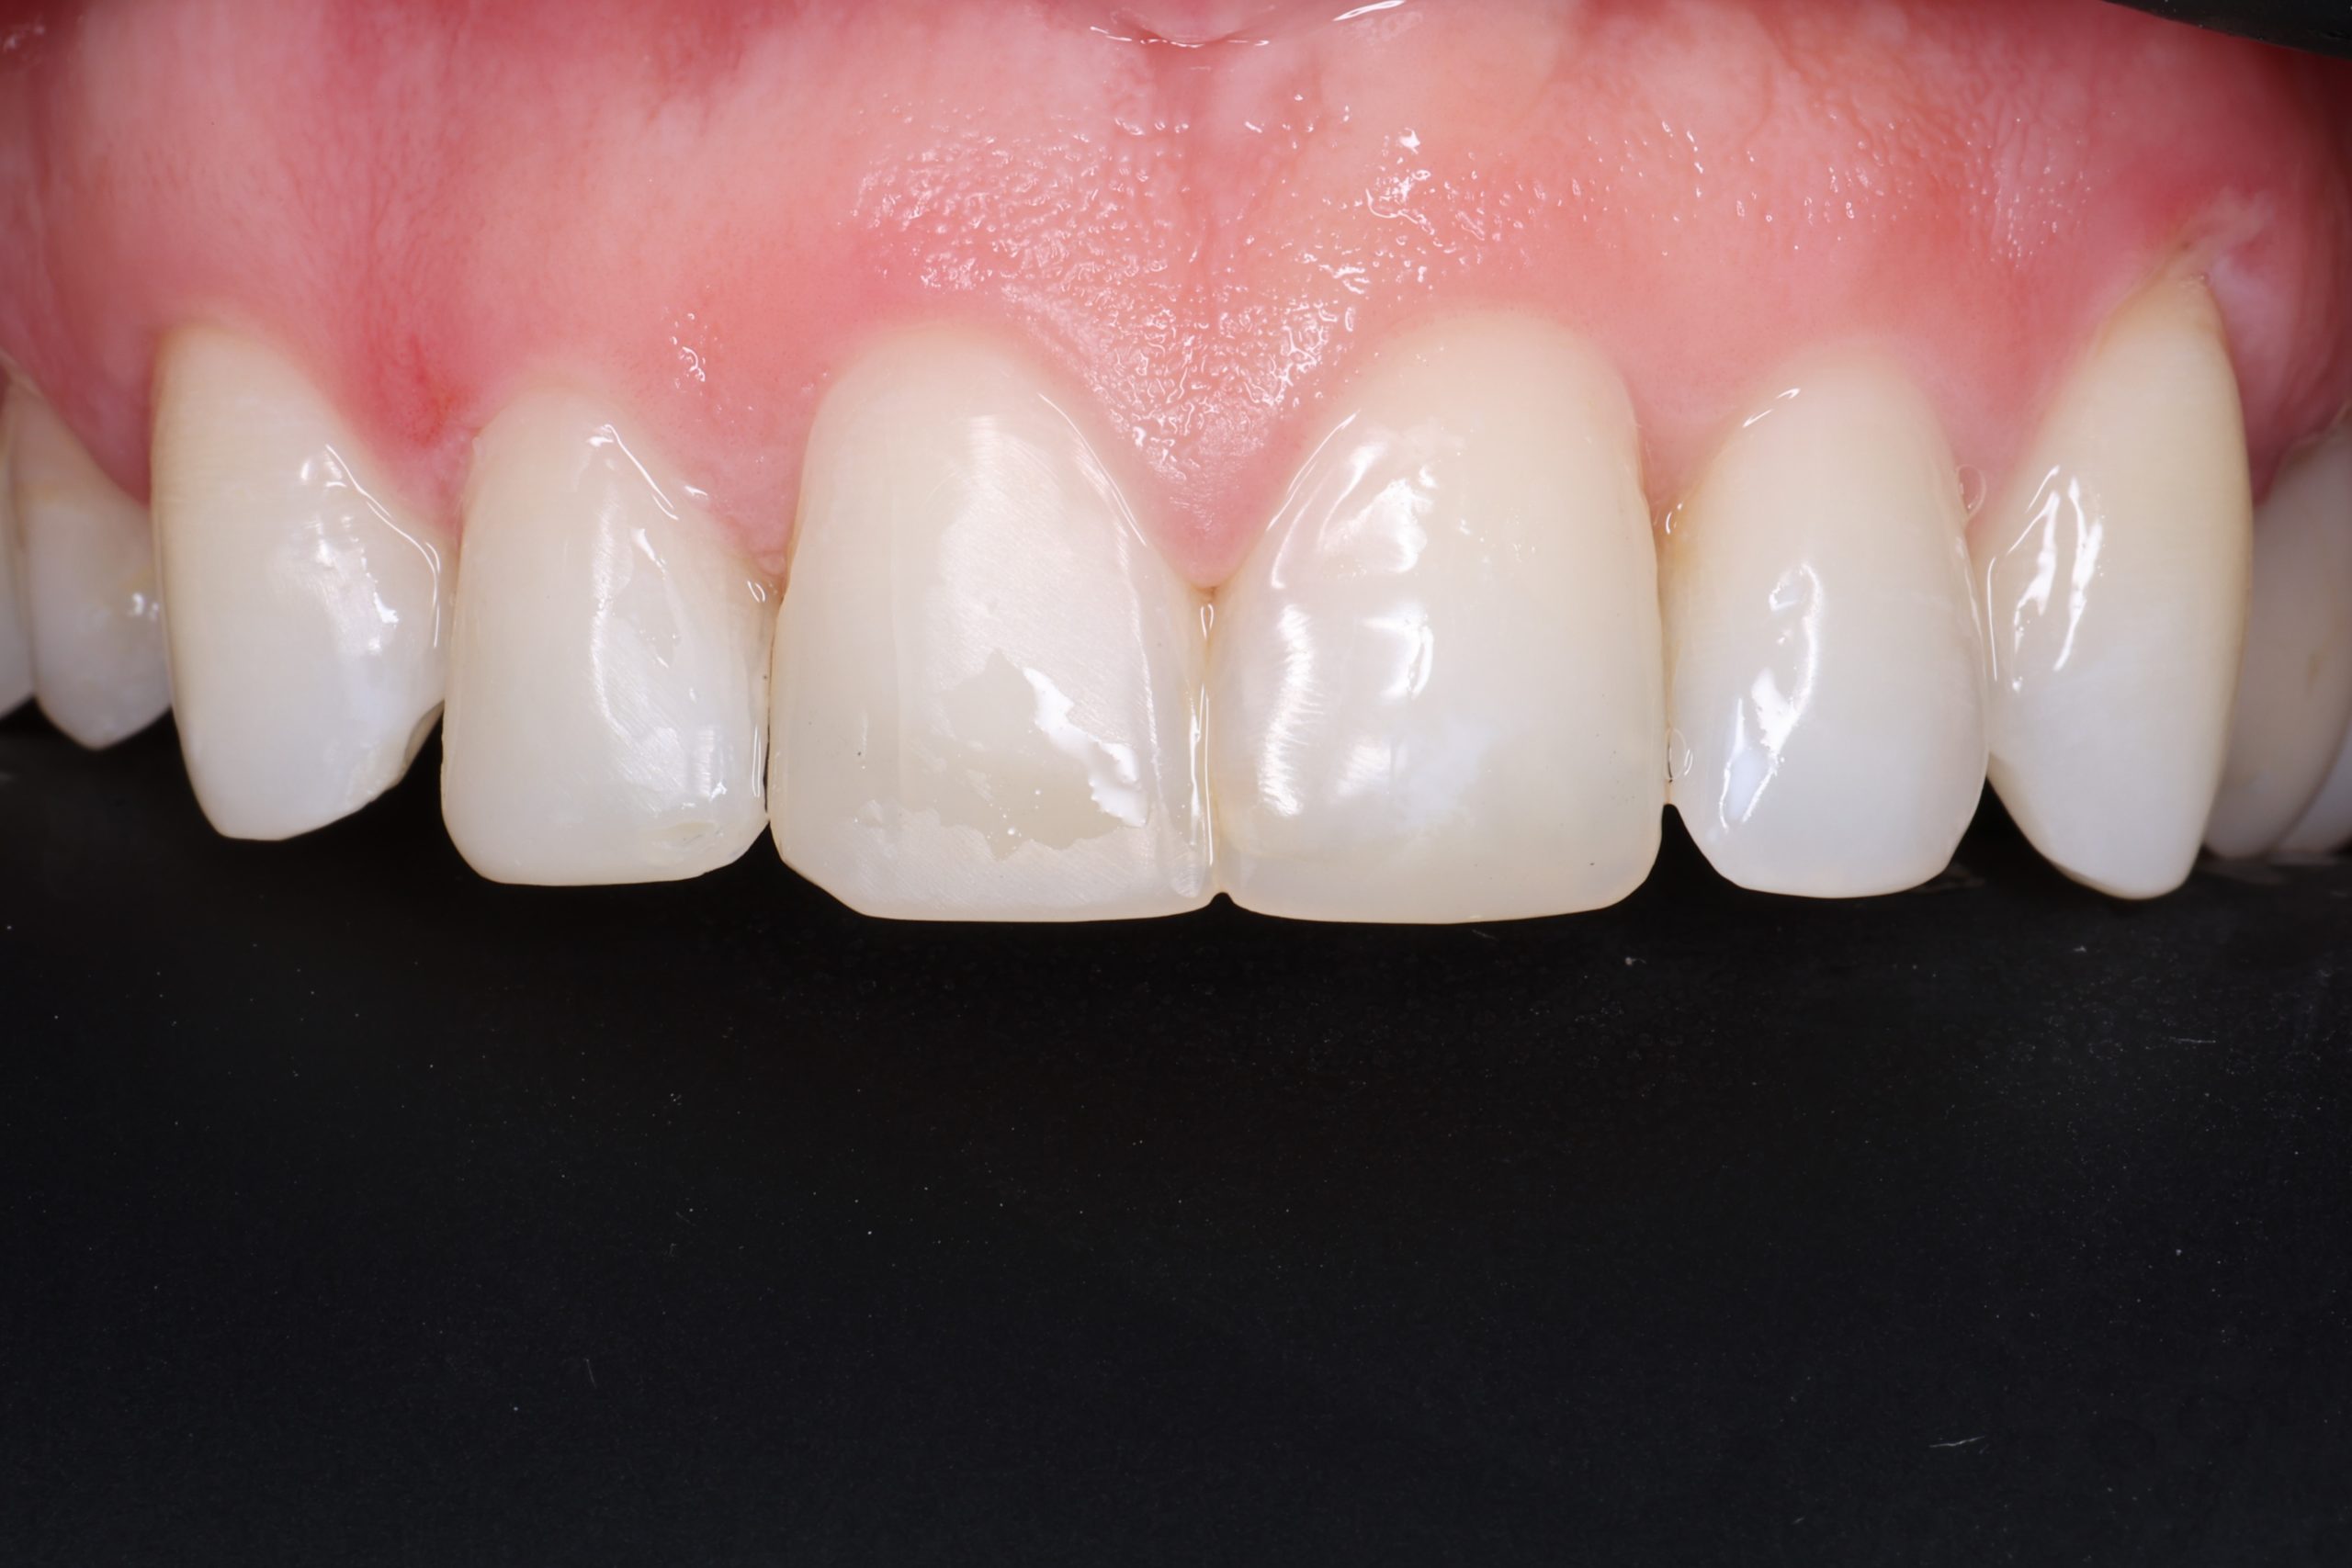

The tooth-coloured resin is applied in thin layers and shaped carefully to match natural anatomy. For front-tooth work, we may combine several shades for a lifelike result.

5. Final Polishing and Bite Adjustment

We contour and polish the surface to a high gloss and ensure your bite feels natural in all positions.

Aesthetic and Natural-Looking

The material matches your enamel, blending into the smile with virtually invisible transitions.

• fixing chipped or worn edges

• closing minor gaps

• correcting tooth shape asymmetry